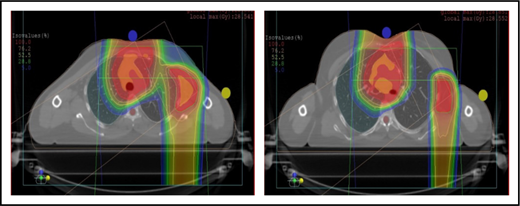

Scans for a young woman in whom the target included mediastinal, left parasternal, and left axillary regions. One anterior field was used for the mediastinum, and a separate posterior field was used for the axillary region.

With regard to field arrangements, the PBSPT technique for an anterior upper mediastinal and lower neck target usually requires 1 (repainted) or 2 anterior fields. For more complex target volumes, targets can be divided into 2 or more parts (eg, neck CTV, mediastinal CTV, and axillary CTV), and a multifield plan can be used (Figure 5). For cases that involve lower (posterior) and upper (anterior) mediastinal targets, a combination of posterior and anterior fields can maximally spare the heart and lungs (Figure 6). For upper neck targets, lateral or posterior fields can avoid the oral cavity/salivary structures. For axillary targets, a posterior field can help to spare breast tissue. Although these various field arrangements can be used in PSPT, gradient matching is simpler in PBSPT when the fields overlap or oppose, obviating the need for feathering.